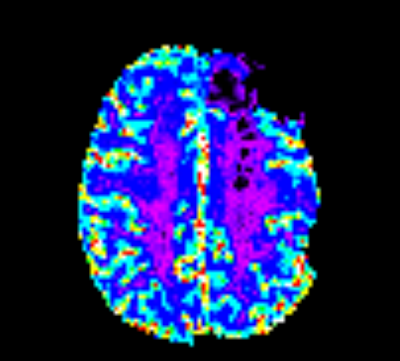

IB Neuro CTP

[en] IB Neuro™ v2.0 analyzes dynamically acquired MR and CT datasets and generates parametric perfusion maps quantifying changes in contrast over time. Advancements in IB Neuro are designed to fit routine clinical and research workflow and address advanced clinical and research needs. Features in IB Neuro™ • Improved automatic generation of Arterial Input Function (AIF) • Rapid creation of a complete array of critical perfusion parameter maps, including TTP and Tmax • Automatic correction of contrast agent leakage across the blood brain barrier for MR DSC • Automated brain mask generation • Ability to standardize and normalize parameters using an exclusive Voxel Intensity Calibration™ technology • Dual-echo GRE support for MR DSC • New calculated images are automatically exported as new DICOM series and can be easily pushed to a PACS IB apps are designed to be compliant with healthcare standards such as DICOM and can be conveniently integrated with ease and speed into existing medical image visualization applications ranging from simple stand-alone workstations to sophisticated, PACS, CAD, MR, and IMRT systems.